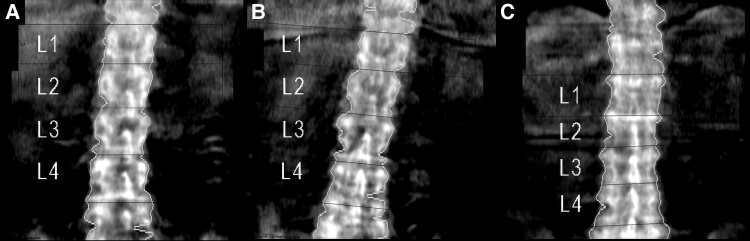

A defect in the canonical Wnt-β-catenin pathway may lead to reduced bone strength and increased fracture risk. Sclerostin is a key inhibitor of this pathway by binding to low-density lipoprotein (LDL) receptor-related protein (LRP)-5/6, thereby reducing bone formation. The effectiveness of romosozumab, a human monoclonal antibody that binds sclerostin and prevents this inhibitory effect, has been questioned in patients with inactivating genetic variants in LRP5 or LRP6. We present a 67-year-old woman with severe osteoporosis with 4 grade 2 vertebral fractures due to a heterozygous pathogenic variant in LRP5. She was treated with romosozumab for 1 year, after which a routine follow-up spine x-ray revealed 5 new vertebral fractures, despite a strong increase in bone mineral density (BMD) (lumbar spine [LS] + 58%; femur neck [FN] + 23%), although overestimated at LS because of the vertebral fractures. This suggests that in patients with loss-of-function LRP5 variants, romosozumab is able to increase BMD. However, it is unclear whether the progressive vertebral fractures are due to the severe osteoporosis in relation to the start of romosozumab or a diminished responsiveness related to her LRP5 variant. Further evaluation is needed on the effect of romosozumab on BMD and fracture outcomes in patients with a likely defective LRP5/6 receptor.